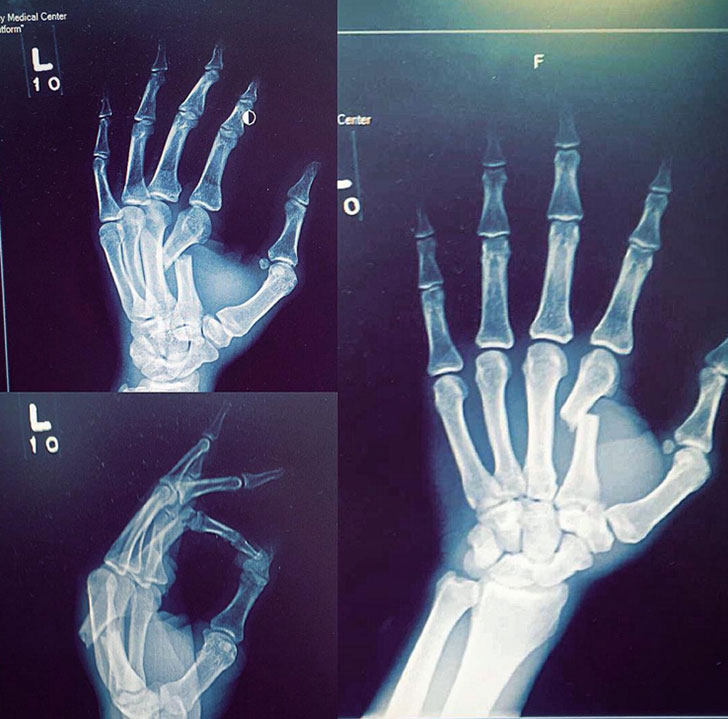

В минувшие выходные на Bellator 145 в Сент-Луисе Дэниел Штраус отобрал титул в полулегком весе у Патрисио Фрейре, причем сделал это одной правой рукой, сломав левую в самом дебюте поединка.

«Доктор мне сказал, что это один из худших переломов, которые он когда-либо видел. А теперь представьте, если бы я не сломал руку в первом раунде», - написал Штраус в Инстаграм, подтвердив свои слова рентгеновским снимком.